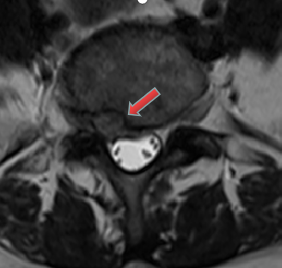

3月前,患者再次出現(xiàn)腰腿痛疼痛癥狀,夜不能寐,嚴重影響生活?;颊邚?fù)查了腰椎磁共振,結(jié)果提示:腰5/骶1椎間盤突出復(fù)發(fā),明顯壓迫神經(jīng)。經(jīng)過口服消炎止痛藥、理療等保守治療,患者腰腿痛無明顯改善,于是再次入住惠州三院脊柱外科,被診斷為復(fù)發(fā)性腰椎間盤突出癥。

核磁共振檢查影像